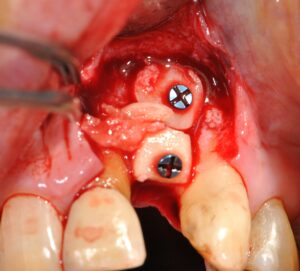

Les techniques de reconstruction osseuse ont évolué dans le sens de la simplification des procédures et des volumes de tissus régénérés.

Nous rappellerons les fondements biologiques de la cicatrisation osseuse, puis une iconographie de cas cliniques permettra de visualiser l’évolution de différentes techniques depuis une vingtaine d’années.